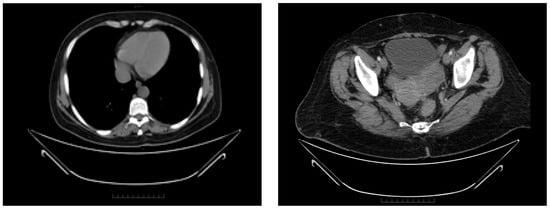

2.2.6. Follow-Up

| January 2022 (progression) | 11.3 | 278,000 | 145.20 |

| June 2022 (after secondary cytoreductive surgery) | 10.1 | 488,000 | 18.65 |

| November 2022 (start Tamoxifen treatment) | 11.7 | 229,000 | 8.66 |

| November 2022–December 2023 | 12.7 * | 190,000 * | 16.37 * |